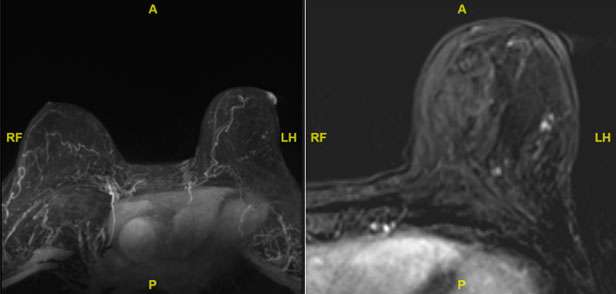

The mammographic findings of Paget’s disease include skin thickening in the nipple areolar complex region, nipple retraction, underlying suspicious calcifications, or a discrete mass. The ultrasound findings include nonspecific heterogeneity of the breast parenchyma, a mass, dilated ducts, and skin thickening or hypervascularity in the nipple areolar complex (Figure 3). Breast MRI may assist in further evaluation in the setting of negative mammogram and ultrasound findings (Figure 4).